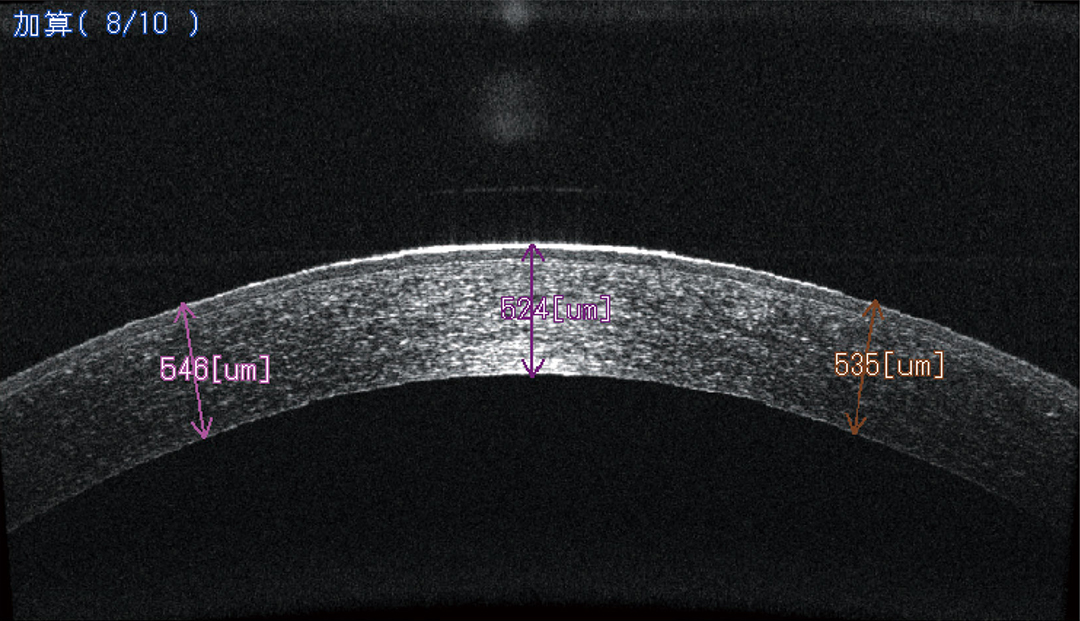

・前眼部OCT

角膜や前房や虹彩や隅角の断層像の観察が非侵襲で可能です。

円錐角膜、角膜移植後の経過観察、急性緑内障発作の診断補助に有用です。